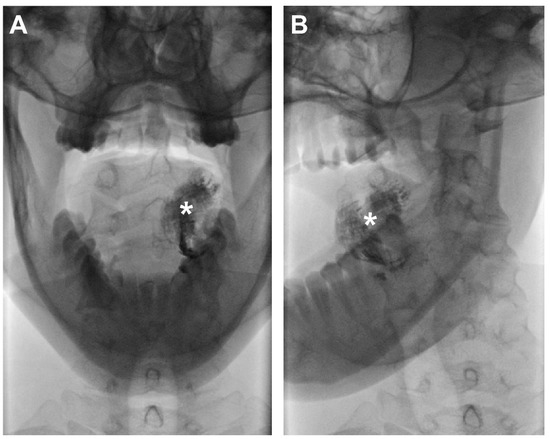

Figure 5.

Low-dose X-ray of extirpated SLNs from patient 6. (A) SLN level Ib left (750 counts per second), which proved histopathologically positive for metastasis, showed no traces of Lipiodol®. (B,C) SLN level Ib left (5387 counts per second; histopathologically negative) and SLN level IIa left (9194 counts per second; histopathologically positive) with the uptake of Lipiodol® as confirmed by low-dose X-ray (white squares).